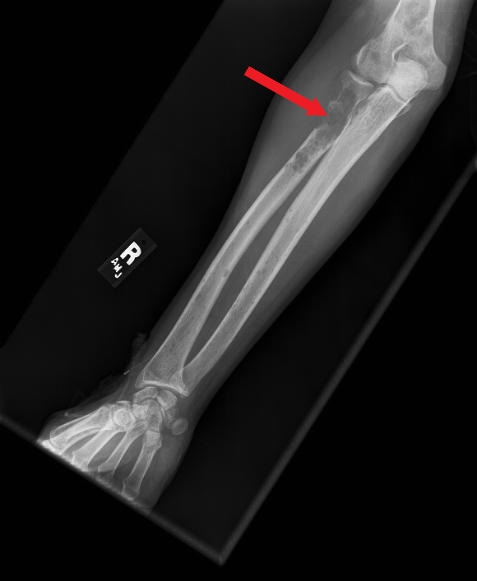

OI

Osteogenesis imperfecta

Pathogenesis

>90% autosomal dominant Type I collagen gene (COL1A1) defect

Clinical features

Mild to moderate Frequent fractures Blue sclera Conductive hearing loss Short to normal stature Dentinogenesis imperfecta Joint hypermobilityLethal (type II) In utero and/or neonatal fractures Pulmonary failure

This patient has osteogenesis imperfecta (OI), an autosomal dominant connective tissue disorder commonly caused by a type I collagen mutation. Type I collagen is a critical structural component of tissues in the bone, sclerae, skin, and teeth. OI has a varying spectrum of severity, from mild (type I) to lethal (type II) disease.

Due to defective collagen in osteoid (extracellular bone matrix), patients often begin having frequent fractures from minor trauma once they become mobile (around age 1). Many patients with OI also have dentinogenesis imperfecta, an opalescent blue-gray or yellow-brown discoloration of the teeth caused by discolored dentin shining through translucent and weak enamel. Joints are often hypermobile due to ligamentous laxity. Scleral thinning can lead to the appearance of blue sclerae; other manifestations depend on the severity of the disorder and may include hearing loss and short stature.